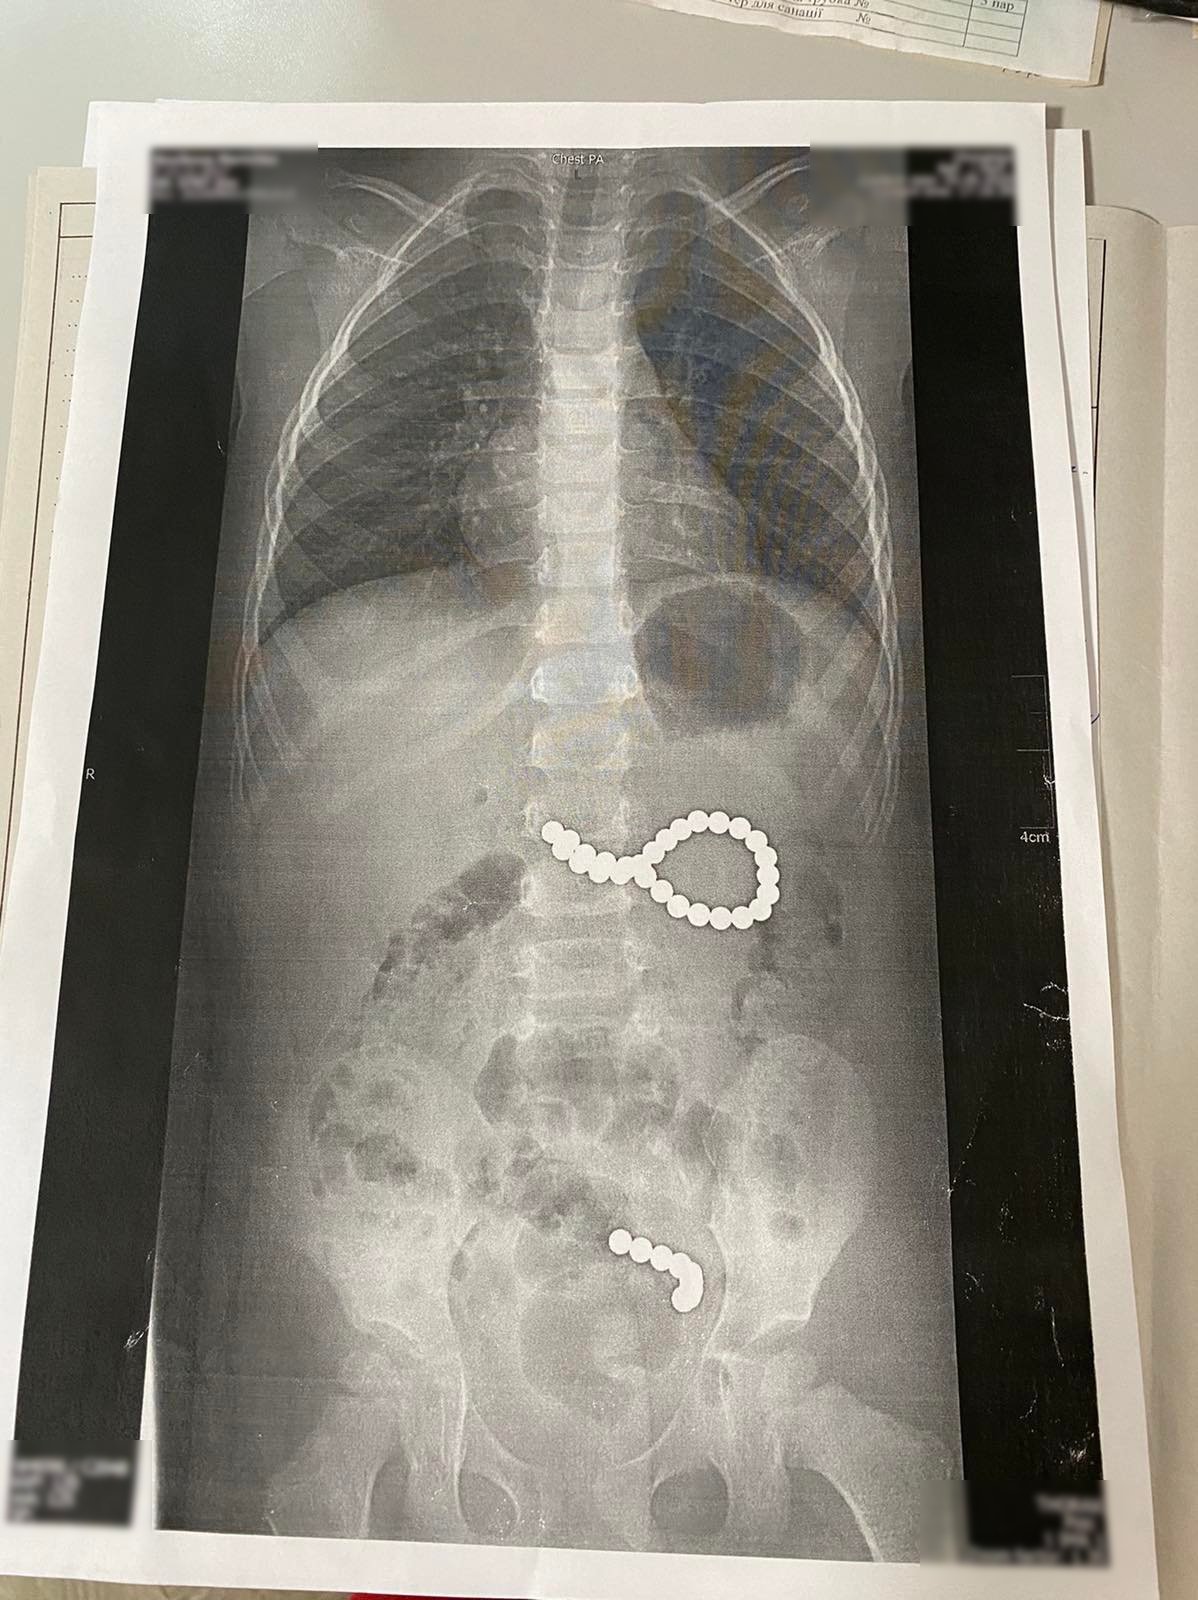

У львівській обласній дитячій лікарні ОХМАТДИТ провели термінову операцію трирічній дівчинці з Дрогобицького району, яка проковтнула 36 магнітних кульок від конструктора. Дев"ять кульок під дією магнітного поля утворили ланцюжок і потрапили в кишківник, ще 27 кульок утворили неправильне коло і потрапити в кишківник не могли. Дівчинку довелося терміново оперувати.

"Дев"ять кульок, які дитина проковтнула у п"ятницю, утворили ланцюжок, бо було сильне магнітне поле. І вони пройшли зі шлунка в тонкий кишківник. А ті 27 магнітних кульок, які дитина проковтнула у суботу, утворили неправильне коло і їх терміново треба було діставати. Кульки були діаметром 4 мм, найвірогідніше, з якогось конструктора", – розповіла лікар Горбач.

Медики намагалися дістати кульки за допомогою ендоскопа під загальним наркозом.

"Спершу нам не вдавалося. Кульки круглі, слизькі, постійно зіскакували з ендоскопічних петель, інших пристосувань. Згодом ми одна за одною дістали 27 кульок. Дев"ять, які потрапили у кишківник, вийшли природним шляхом", – розповіла хірург.